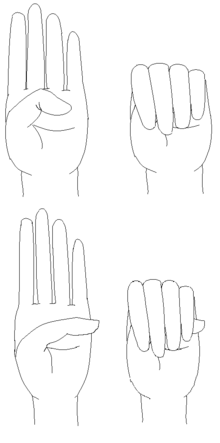

A positive wrist sign in a person with Marfan syndrome (the thumb and little finger overlap, when grasping the wrist of the opposite hand).[1] | |

- Wrist AND thumb sign = 3 (wrist OR thumb sign = 1)

The thumb sign (Steinberg's sign) is elicited by asking the patient to flex the thumb as far as possible and then close the fingers over it. A positive thumb sign is where part of the thumb is visible beyond the ulnar border of the hand, caused by a combination of hypermobility of the thumb as well as a thumb which is longer than usual.

The wrist sign (Walker's sign) is elicited by asking the patient to curl the thumb and fingers of one hand around the other wrist. A positive wrist sign is where the little finger and the thumb overlap, caused by a combination of thin wrists and long fingers.[38]